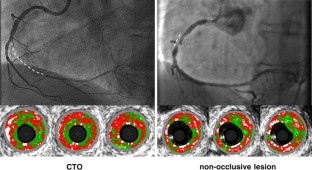

To use virtual histology intravascular ultrasound (VH-IVUS) to assess the differences in tissue composition between chronic total occlusions (CTO) and non-occlusive lesions, especially in vivo. We compared 50 CTOs (49 patients) after guidewire crossing with 41 non-occlusive lesions (41 patients, 25 with unstable angina and 16 with stable angina). Overall, the percentage of necrotic core in the CTO segments was similar to non-occlusive lesions (35.6 vs. 38.7 %, p = 0.18 at the maximum necrotic core site; 24.2 vs. 23.7 %, p = 0.8 in mean analysis over the entire segment length). However, the percentage of dense calcium in CTO segments was less than in non-occlusive lesions (10.6 vs. 14.8 %, p = 0.025 at the maximum necrotic core site; 7.6 vs. 11.4 %, p = 0.036 in mean analysis over the entire segment length). Finally, the necrotic core/dense calcium ratio tended to be larger in the CTO segment than in non-occlusive lesions (2.94 vs. 2.35, p = 0.082 at the maximum necrotic core site; 3.05 vs. 2.03, p = 0.005 in mean analysis over the entire segment length). Overall, 42 (84 %) CTOs contained a fibroatheroma compared to 40 (97 %) of non-occulsive stenoses. The percentage of necrotic core in CTOs with a fibroathroma (39.0 %) was less than non-occlusive stenoses with a VH-thin cap fibroathroma (44.4 %, p = 0.017) and greater than non-occlusive stenoses with a VH-thick cap fibroathroma (33.5 %, p = 0.022) at maximum necrotic core site. These findings suggest that the morphological characteristics of most CTOs were similar as compared with non-CTO lesions and CTOs evolved from fibroatheromas.

Fig. 1